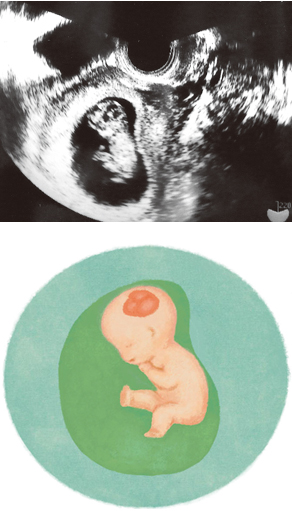

妊娠10週ころのエコー写真を見てみよう

小さな手足が見えてきます

ヒトの形に近づいてきて、頭、手、足の区別がわかるようになります。手足を活発に動かす赤ちゃんもいます。写真は片方の足を伸ばした姿勢で、頭の黒い部分は脳です。